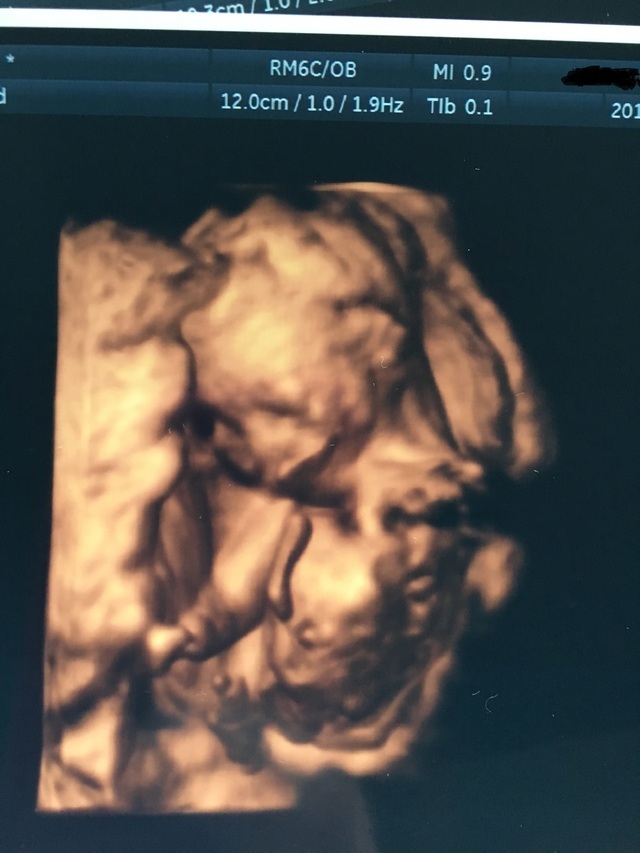

18週1日(18w1d・性別不明)|ぴーさよ さん(30歳)

エコー写真撮影時のエピソード:

初めての4Dエコーでした。 いつも見てるエコーとは違い立体的に見えて愛しさが増しました(^^) 他の人がこれを見たらただのホラー写真ですが。

少し恥ずかしいのか横を向いて隠れようとしていました!正面ではないけどお口をパクパクと動かしてくれて元気一杯で先生にも順調ですねと言われとても安心したのと、ほんとにお腹にいるんだなぁーって改めて思いました(^^)